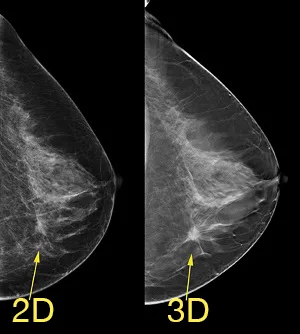

What is a 3D Mammogram (DIGITAL BREAST TOMOSYNTHESIS) ?

Trinity is one of 6 medical service providers in Hong Kong using this machine. This instrument can detect 41% more invasive cancer than other mammography, and the degree of reliability is incomparable.

Advantage of 3D MAMMOGRAM

- Detects 41% more invasive cancers.

- Reduce false positive recalls by up to 40%.

- Clinically superior exams with comparable radiation dose to conventional 2D imaging.